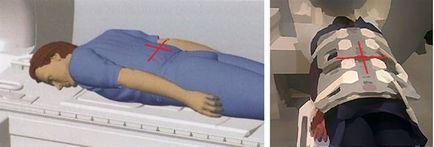

A helyzet a kutatás

- A helyzet a fekvő beteg gyomra felé fordította a fejét a mágnes (a gyomra, fejjel előre);

- A beteg felett van elhelyezve, a gerinc tekercs és a tekercs van felszerelve, hogy a test fölött a felső fele a has és a medence (magában foglaló régiót a mellbimbó a glutealis szeres);

- Biztonságosan rögzítse a tekercset, hogy a test útján bilincsek megelőzésére légzési műalkotás;

- Az extra kényelem, hogy a beteg egy párnát a feje alá, és forgassa a lába alatt;

- A központi lézersugár középpontjában fölött a gerincet a csípő.

Scan képek fekvő helyzetben ajánlott, hogy javítsa a gyomor kiürülését és jobb vizualizációs a bél hurkok